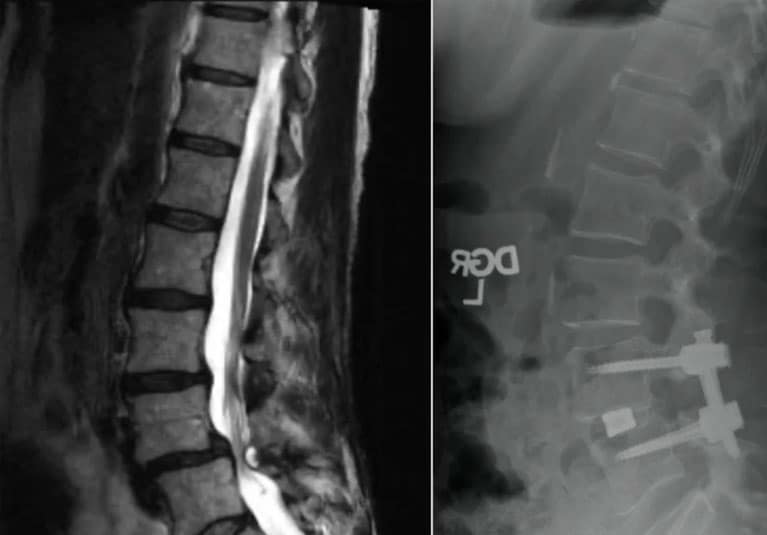

在左图中,术前 MRI 显示了在妙佑医疗国际进行清醒微创经椎间孔入路腰椎间融合术(MIS-TLIF)前的脊柱弯曲。在右图中,术后图像显示了清醒手术期间实现的校正。

Mayo Clinic's spinal anesthesia protocol is used for selected individuals undergoing laminectomy, diskectomy or minimally invasive surgery-transforaminal lumbar interbody fusion (MIS-TLIF). The procedures are completed within 2 to 3 hours — the typical duration of spinal anesthesia.

Mayo Clinic's techniques for safely performing awake MIS-TLIF are described in a technical note published in the January 2021 issue of the Journal of Clinical Neurology and Neurosurgery. The procedure is used only for one- or two-level fusions due to the time constraint of spinal anesthesia. Mayo Clinic further enhances awake MIS-TLIF by using robotic technology to guide screw placement.